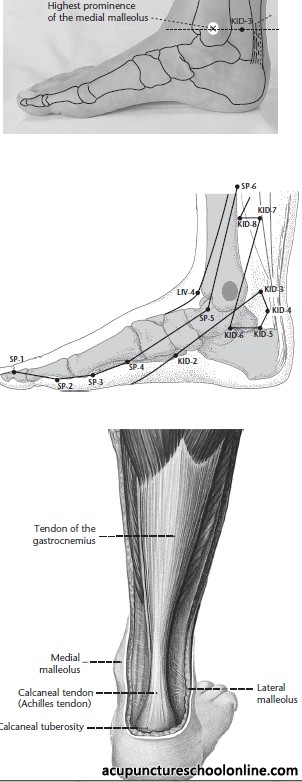

In the depression between the medial malleolus and the Achilles tendon, level with the prominence of the medial malleolus

Along with Shuiquan Kid-5 this is a possible location for the posterior tibial pulse. The ideal location is halfway between them at Pimenta's Point, the exact midpoint of a line drawn between the bony prominence of the medial malleolus and the insertion of the Achilles' tendon.

Basic information on location, needle depth, TCM actions, indications and combinations is taken from Deadman et al (2001): A Manual of Acupuncture with additional anatomical information researched by reference to Gray's Anatomy (38th Ed., 1995) unless otherwise referenced. Images were found on acupunctureschoolonline.com and can be traced back to Claudia Focks (2008) Atlas of Acupuncture originally. I cannot claim any credit or rights over them. Other sources should be quoted in the text.